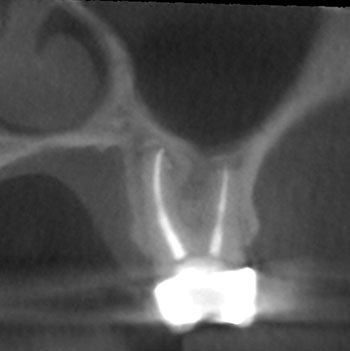

Case 5: Bilateral lesions

This patient was very worried that she was going to lose her front tooth, #8. Her dentist was concerned that the root had been split by a large, tapered post given the context of the bilateral radiolucencies located at the bottom of the post.

No crack was seen when the post was removed, nor were any lateral canals located. This tooth was treated in three visits over six months using a calcium hydroxide intracanal medicament. It is possible that a nidus of bacteria remained in the gap between the obturation and the post.

The patient’s symptoms resolved after the first visit. The case was obturated after confirming full bony healing. She is still extremely appreciative of the efforts made to save her front tooth.

Fig. 19: Preop PA.

Fig. 20: Preop CBCT.

Fig. 21: Recall PA.

Fig. 22: Recall CBCT.